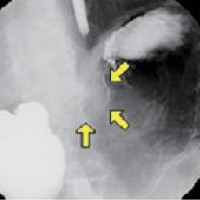

기초검사와 일반검사에서 얻은 자료를 토대로 각종 영상판독 소견을 종합하여 종합검진결과를 완성합니다. 검진결과를 참고하여 필요한 경우에는 개인맞춤 처방을 제공합니다. 또한 내과외래 진료도 진행하여 환자들의 내과진료를 담당합니다. 소화기 내과에서는 위/대장 내시경 검사 및 판독결과 상담을 통해 소화기질환 및 암검진에 대한 상담 및 처방을 진행합니다.